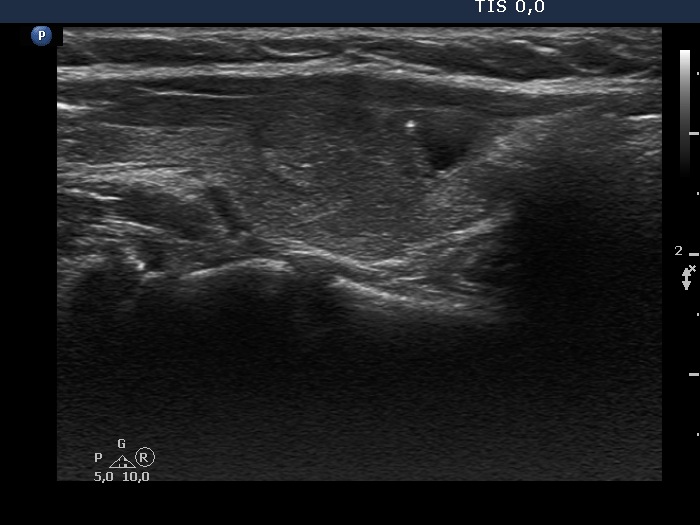

Ultrasonography. The thyroid was echonormal or minimally hypoechoic. There was a moderately hypoechoic nodule which had a cystic portion in the lower part. The nodule had lobulated margins and contained different hyperechoic figures. Beside figures caused either by posterior enhancement of proliferation of connective tissue, several ambiguous. bright granules were also found. Compared with the first measurement, the nodule is increased by more than 75% in volume.